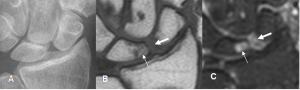

Edema óseo en muñeca